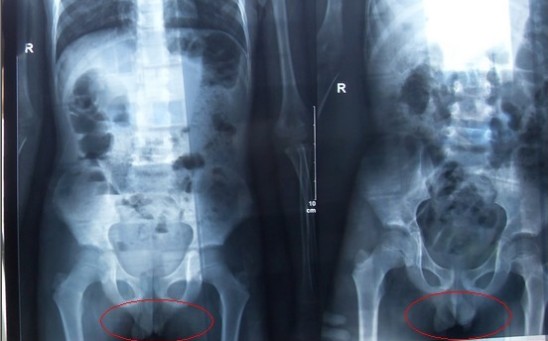

醫(yī)療X光機(jī)的拍攝方式和基本原理與長(zhǎng)途汽車站的X射線行李安檢機(jī),其實(shí)是一樣的,只是劑量的不同而已,但很多人估計(jì)會(huì)有疑問(wèn):X射線的輻射是否會(huì)對(duì)人體造成傷害,會(huì)不會(huì)影響正常的成長(zhǎng)和發(fā)育? &nbs...